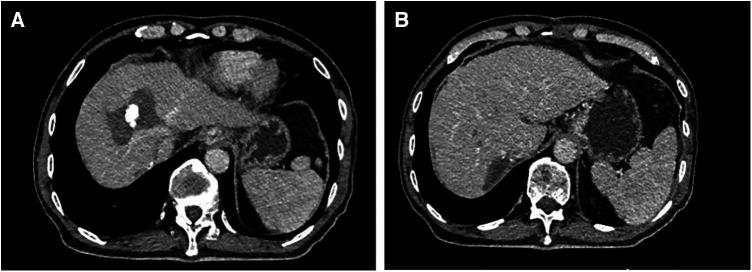

Forty-five consecutive patients with multiple HCCs who met the inclusion criteria received downstaging treatment with TKIs plus anti-PD-1 antibodies combined with TACE. Nine patients were successfully downstaged and met the R0 resection criteria, and 8 patients underwent surgery. Among the patients, 5 patients had BCLC stage C, and 3 patients had BCLC stage B. There were 2 lesions in 5 patients, 3 lesions in 2 patients, and 4 lesions in 1 patient. The average size of the main HCC was 8.5 cm (range: 5.4-9.1 cm), and the diameter of the remaining HCCs was 1.6 cm (range: 0.8-2.9 cm). The average time from the start of downstaging therapy to surgery was 81 days (range: 60-210 days). All 8 patients underwent LH of the main HCC, and the remaining HCCs were targeted with RFA. The mean operation time was 220 min (range 150-370 min), the average intraoperative blood loss was 260 ml (range 100-750 ml), there was no case conversion to laparotomy, and the average postoperative hospital stay was 9 days (range 7-25 days). The incidence of postoperative complications was 37.5% and there were no deaths. The average follow-up time was 18.2 months (range 6.1-22.4 months), 5 patients survived tumour-free, 2 patients had tumour recurrence, and 1 patient died.

45例符合纳入标准的连续多发性肝癌患者接受了TKIs联合抗PD-1抗体并结合TACE的降期治疗。9例患者成功降期并符合R0切除标准,8例患者接受了手术。患者中,5例为巴塞罗那临床肝癌(BCLC)分期C期,3例为BCLC分期B期。5例患者有2个病灶,2例患者有3个病灶,1例患者有4个病灶。主要肝癌的平均大小为8.5 cm(范围:5.4 - 9.1 cm),其余肝癌的直径为1.6 cm(范围:0.8 - 2.9 cm)。从降期治疗开始到手术的平均时间为81天(范围:60 - 210天)。所有8例患者均接受了主要肝癌的LH,其余肝癌采用RFA靶向治疗。平均手术时间为220 min(范围150 - 370 min),平均术中出血量为260 ml(范围100 - 750 ml),无病例转为开腹手术,平均术后住院时间为9天(范围7 - 25天)。术后并发症发生率为37.5%,无死亡病例。平均随访时间为18.2个月(范围6.1 - 22.4个月),5例患者无瘤生存,2例患者肿瘤复发,1例患者死亡。